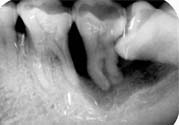

5、如果智齒經(jīng)常疼,而且疼的比較厲害,可能已經(jīng)引發(fā)牙冠周軟組織發(fā)炎,所以導(dǎo)致智齒腫脹、疼痛;再如果智齒長(zhǎng)的位置很歪,影響其它牙齒正常咀嚼,也影響美觀,最好是考慮拔牙。拔牙前提是確保牙冠周?chē)鷽](méi)有炎癥,才能安排拔牙,免除后顧之憂(yōu),拔智齒是拔牙里最難的一種,所以一定要到正規(guī)口腔醫(yī)院,請(qǐng)正規(guī)醫(yī)師進(jìn)行專(zhuān)業(yè)拔牙。

1、冠周炎:智齒因阻生而使牙冠不能完全外露,牙冠周?chē)难例l成袋狀,極易積存食物、滋養(yǎng)細(xì)菌。當(dāng)全身抵抗力下降時(shí)引起急性冠周炎。

3、第二磨牙齲壞:向前傾斜的阻生智齒,因經(jīng)常在鄰牙間積存食物,易發(fā)生鄰牙(下頜第二磨牙)齲壞。